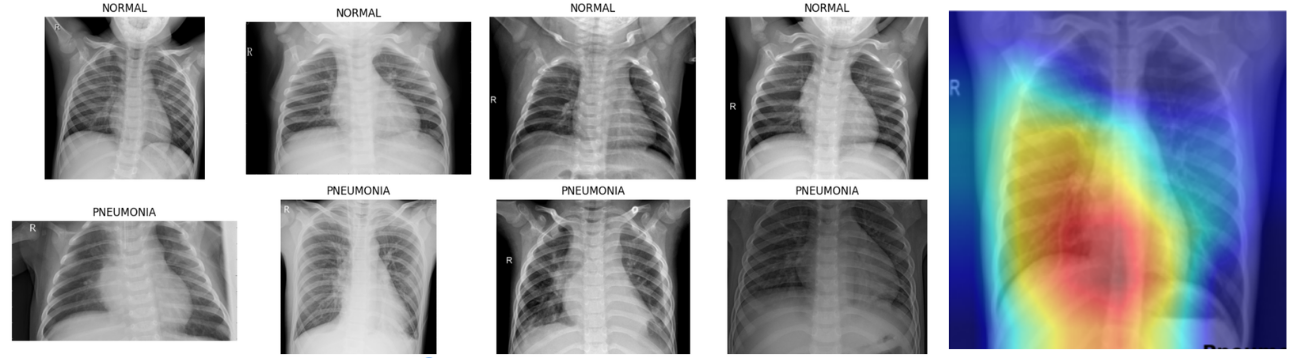

Emil a ainsi développé une intelligence artificielle capable de détecter une pneumonie à partir de radiographies pulmonaires. « Ce projet était assez complexe et lourd, mais il m’a vraiment permis de mettre en application ce que nous avions appris en cours tout en me formant sur des technologies non abordées jusque-là ».